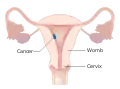

Stage I choriocarcinoma

Stage I choriocarcinoma Stage 2 choriocarcinoma

Stage 2 choriocarcinoma Stage 3 choriocarcinoma

Stage 3 choriocarcinoma Stage 4 choriocarcinoma

Stage 4 choriocarcinoma